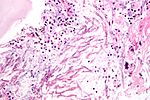

Mucormycosis

General

• Causative organism: Mucorales.

• Kingdom: Fungi.

• AKA Zygomycota (zygomycosis).

• Associated with diabetes, immunodeficiency.

Microscopic

Features:[5]

• Branching hyphae with variable width.

• Granulomata associated.

Notes:

• Not septated.

• Branching angle typically ~90 degrees.